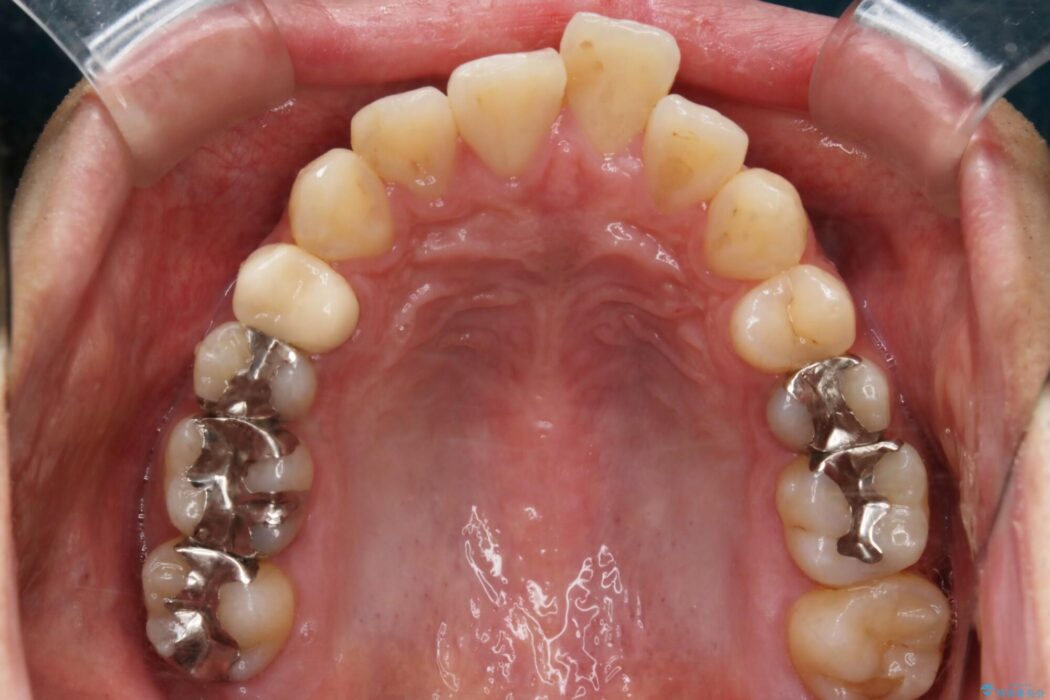

目立たない矯正装置をご希望でしたのでマウスピース装置(インビザライン)をご提案しました。

装置の範囲内で可能な限り前歯の位置を動かし整えるため、マイクロインプラントを用いて遠心移動をする歯列矯正を計画しました。

本症例では上顎前突(出っ歯)や歯列のがたつきを改善するスペースを確保するために、歯を遠心移動をサポートすることができるマイクロインプラントを用いたゴムかけを行っていただきました。

それにより従来の矯正治療と比べましても効率的に歯の移動を行えるため、非抜歯の場合でも歯列を整えることが可能となります。